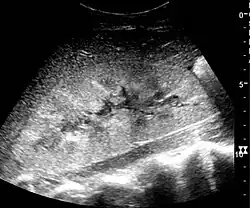

In medical imaging, the acute changes in the kidney are often examined with renal ultrasonography as the first-line modality, where CT scan and magnetic resonance imaging (MRI) are used for the follow-up examinations and when US fails to demonstrate abnormalities. In evaluation of the acute changes in the kidney, the echogenicity of the renal structures, the delineation of the kidney, the renal vascularity, kidney size and focal abnormalities are observed.[16] CT is preferred in renal traumas, but US is used for follow-up, especially in the patients suspected for the formation of urinomas. A CT scan of the abdomen will also demonstrate bladder distension or hydronephrosis. However, in AKI, the use of IV contrast is contraindicated as the contrast agent used is nephrotoxic.